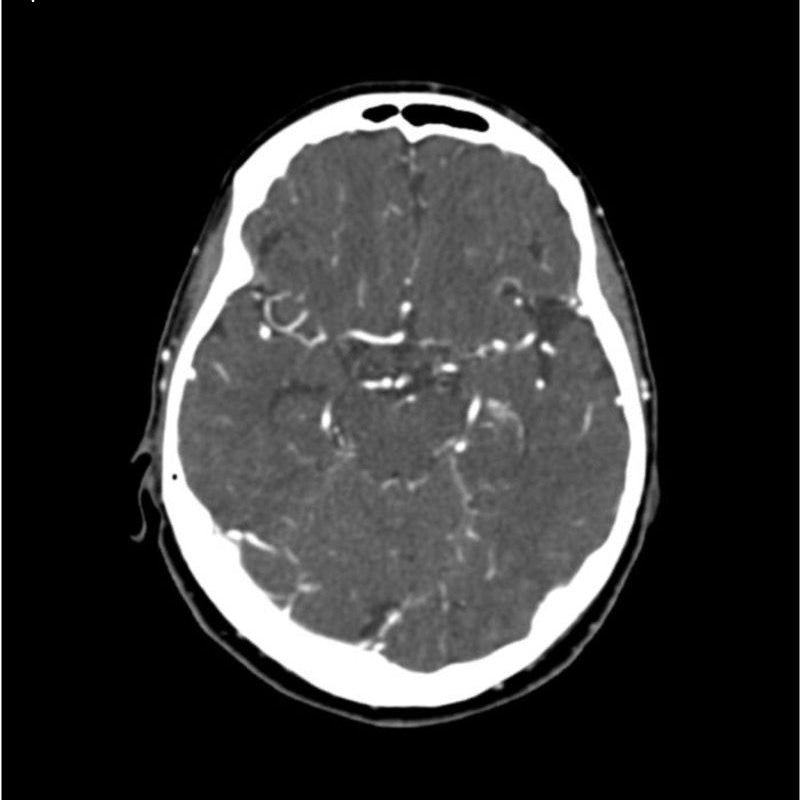

This phantom simulates a contrast medium enhanced head in arterial phase (CT angiography). The neck and upper thorax are included up to the aortic arch and the fifth thoracic vertebra. The vertex is included until approximately 0.5 cm below skin level. The thoracic phantom section excludes shoulder and back parts that are typically not part of CTA examinations. The interncal carotid artery has calcifications on both sides with moderate stenosis on the right side. Otherwise, the phantom has no significant vascular pathologies.

The phantom can be used in CT (including CBCT) to evaluate and optimize CTA imaging performance and post-processing applications such as vessel segmentation, including AI-enabled applications. It is also nicely suited for training purposes. The phantom provides a detailed and realistic simulation of vascular structures, soft and bone tissue, including small details such as lymph nodes. Air voids are filled with a cellulose-polymer composite of approx. -160 HU.

Realistic simulation of head and neck vessels up to the aortic arch, bone and soft tissues.

Calcifications of the internal carotid artery at the carotid bifurcation on both sides with mild stenosis on the right side.